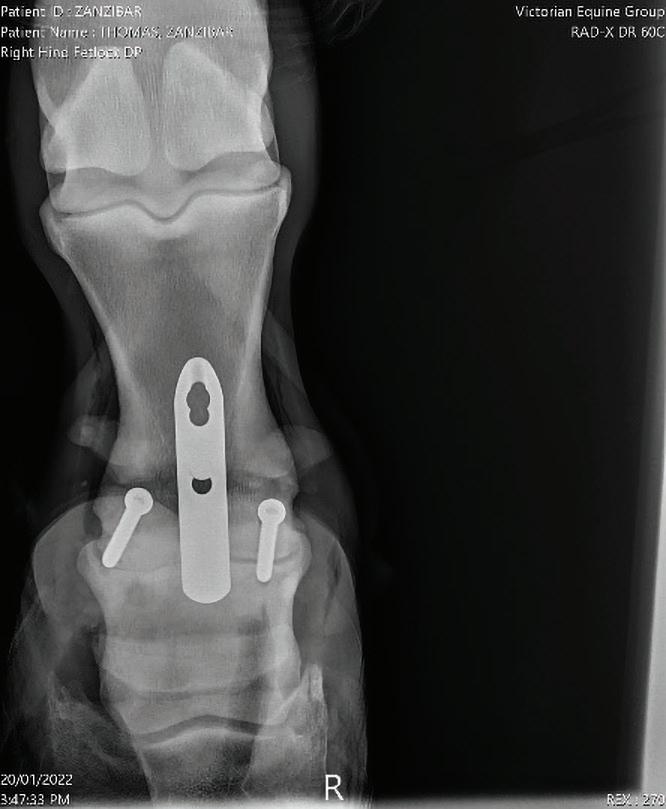

Case Report – Proximal interphalangeal (PIP) joint arthrodesis in a warmblood

32